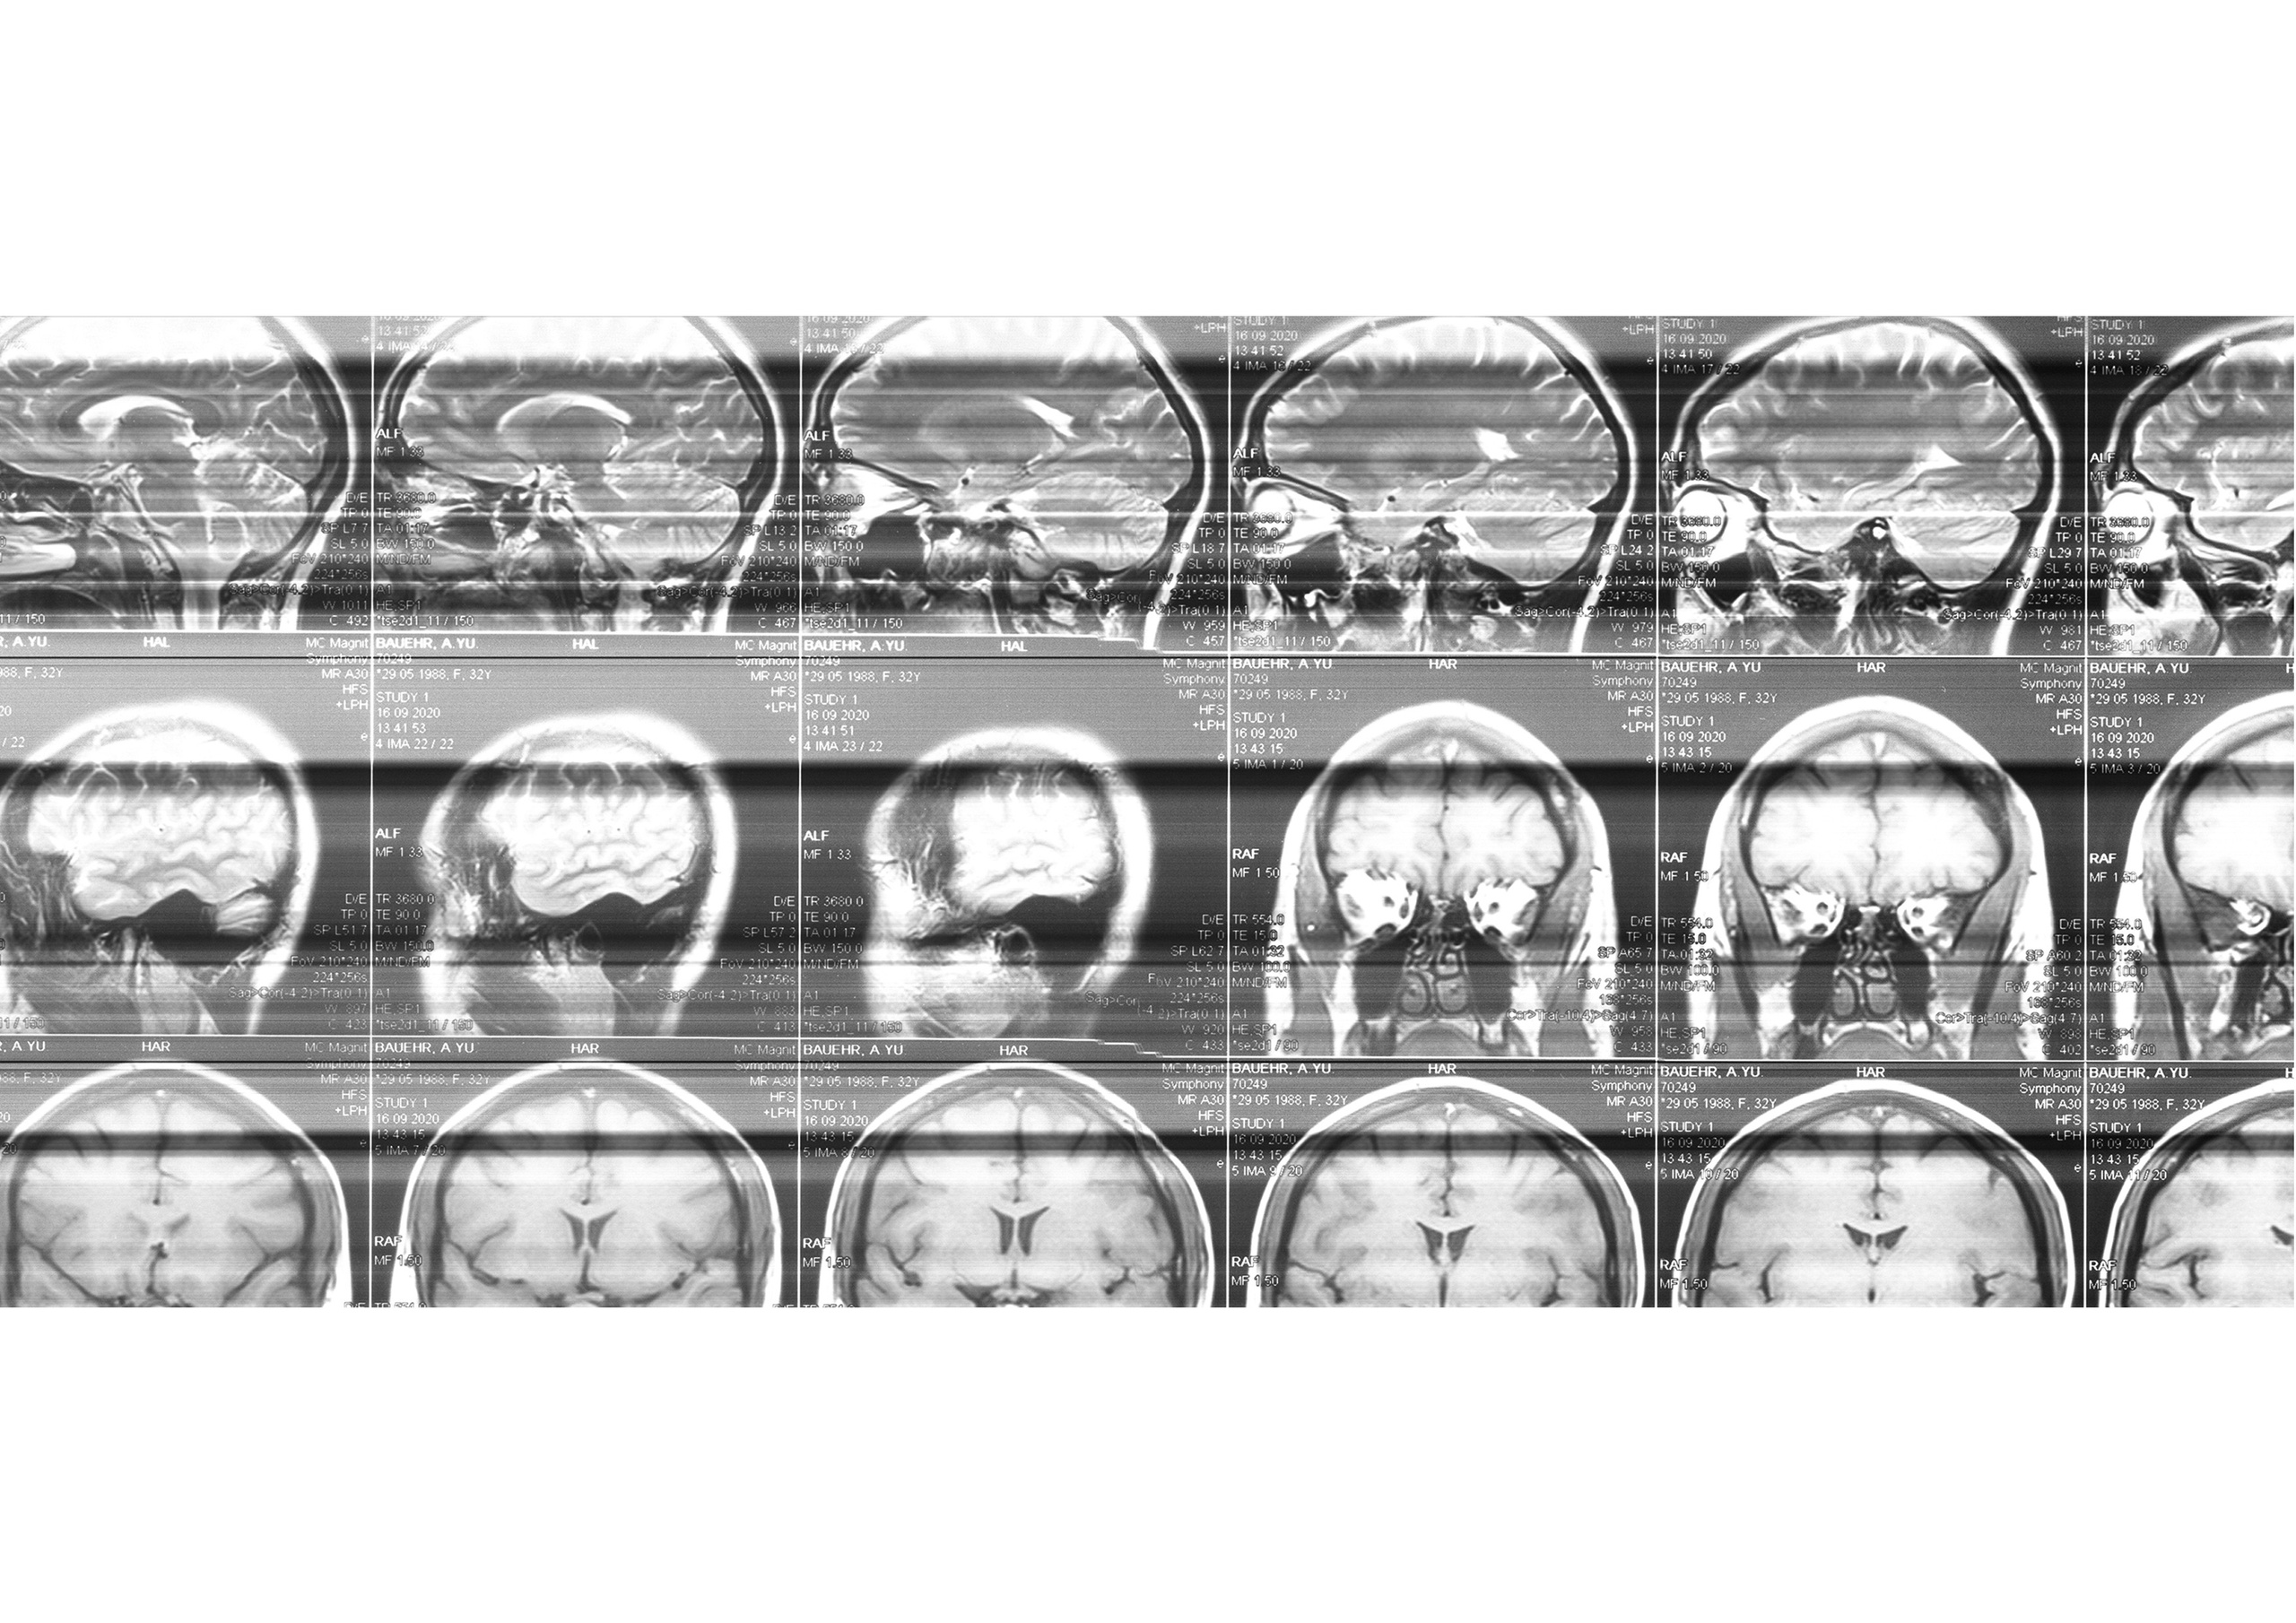

«Каждый сентябрь в моей аптечке появляется новый антидепрессант, прописанный неврологом, который я вскоре бросаю пить от ужасных побочных эффектов. Я часто страдаю от невыносимой головной боли и бессонницы, которые обостряются осенью. У меня нет серьезного медицинского диагноза, здоровый мозг, как подтвердило МРТ исследование. Есть застой венозной крови в шейном отделе зажатая шея и плечи — в какой-то степени это даже вариант нормы.Но я не сплю.Ужас очередной бессонной ночи меня преследует каждый вечер. Мне страшно идти в постель.